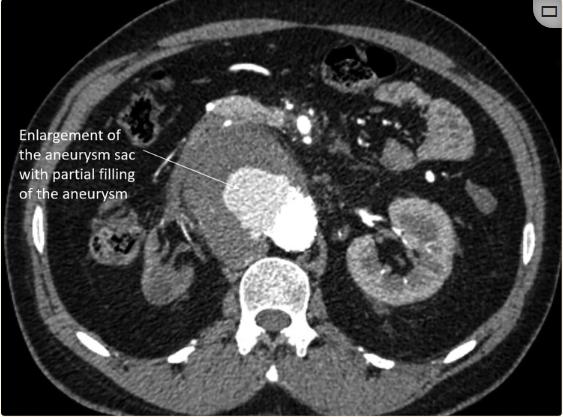

每六个月对病人进行一次CT主动脉造影随访。在两次为期两年的随访中,CT血管造影显示腹主动脉囊状动脉瘤因IB型内漏而增大(图3)。内漏是由于肾下主动脉疾病的远端进展。通过在远端部署28×28×100 TAA支架移植物对其进行管理(图4)。通过部署6×27mm支架来加固左肾支架。术后主动脉造影证实动脉瘤被排除,SMA和左肾动脉血流通畅。后续CT显示动脉瘤段完全排除(图5)。患者每天服用75毫克阿司匹林、抗高血压药、口服泼尼松龙和托法替尼。

图3、后续CT。两年后的CT显示腹主动脉囊状动脉瘤的对比增强和动脉瘤的增大